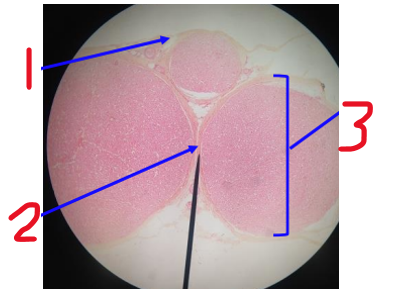

Name 1

perineurium

Name 2

endoneurium

Name the dot at 3

axon

Name the white surrounding the dot at 3

myelin sheath